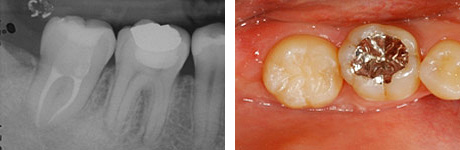

移植後4年。親知らずが第一大臼歯の代わりを担っています。

4年後。移植後に根が少し成長しているのが分かります。歯の神経もつながっています。